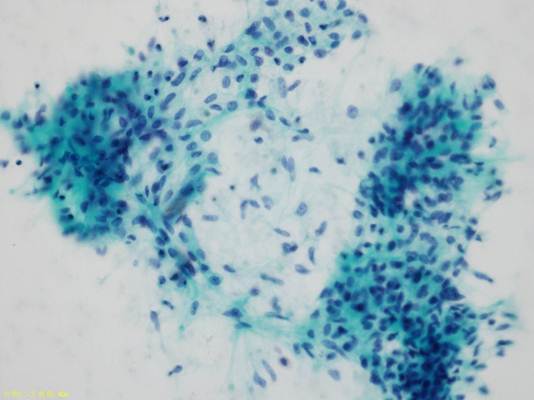

他の視野では重積性があり辺縁にほつれのある細胞集塊や平面的に配列する上皮集塊が認められる。

この集塊の細胞の核は大小不同があり、不整形で核クロマチンが濃染し核小体が目立つ。

細胞質は広く好酸性顆粒をもつものもある。

癌細胞であり多形腺腫由来癌が考えられる。